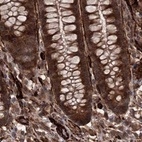

Immunohistochemical staining of human cerebral cortex, colon, fallopian tube and testis using Anti-RPAP3 antibody HPA038312 (A) shows similar protein distribution across tissues to independent antibody HPA038311 (B).